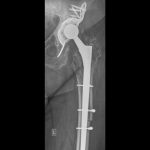

Οι συχνότερες αιτίες αποτυχίας μιας αρθροπλαστικής είναι η η χαλάρωση των μοσχευμάτων, η αστάθεια και το εξάρθρημα της αρθροπλαστικής, τα περιπροθετικά κατάγματα και η πιο δύσκολη επιπλοκή της μολυσμένης αθροπλαστικής.

Κάθε περίπτωση έχει ιδιαιτερότητες που σχετίζονται με το είδος της αρθροπλαστικής που πρέπει να αναθεωρηθεί, με τον τρόπο που θα αφαιρεθούν οι παλιές προθέσεις, με την τεχνική κάλυψης των οστικών ελλειμάτων που συνήθως υπάρχουν στην περιοχή, με τον τρόπο που πρέπει να στερεωθούν τα καινούργια υλικά, με τον χειρισμό των μαλακών μορίων κ.α.

Στις περισσότερες περιπτώσεις η επέμβαση αναθεώρησης των αρθροπλαστικών δεν έχει καμία σχέση με τις τεχνικές και τα υλικά που χρησιμοποιούνται στις αρχικές αρθροπλαστικές.